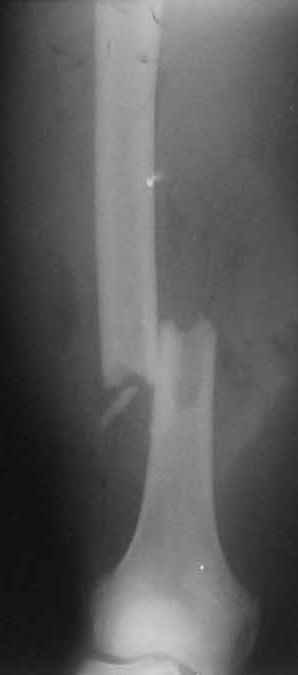

В приложении пример огнестрельного ранения бедра, оперированного на 2 сутки после ранения.

Штифтование было выполнено только на вторые сутки по причине задержки перевода из другого госпиталя, АБ профилактика была начата в другом учреждении, с момента госпитализации пациента к ним. Входное пулевое отверстие и зона введения штифта зажили первичным натяжением.

В конце 90-ых попалось несколько статей по nail exchange procedures in treatment of posttraumatic osteitis и решился попробовать на огнестрельных переломах, которые до этого лечил по полной схеме:расширенный дебрайдмент+ внешняя фиксации+промывные системы с антибиотиками и без антибиотиков в промывной среде. Всё заканчивалось длительной госпитализацией, плохими функциональными результатами( страдала функция колена), необходимостью повторной хирургией - отсроченная внутренняя фиксация переломов, длительной реабилитацией. На гвоздях процесс пошел лучше: остеомиэлитов не было и больные мобилизовывались быстрее.

Единственно что наблюдал - замедленная консолидация, судя по серийным Рг граммам. В приведенном случае прии вялом мозолееобразовании сделал ошибку, решившись динамизировать гвоздь - перелом сросся со значительным укорочением бедра - повторная хирургия по удлинению бедра и проксимальным запиранием, больной мобилизован и вполне доволен(кстати заметить больной с ВИЧ инфекцией - изначально скомпрометированный иммунитет и несмотря на это, всё прошло без костной и мягкотканной инфекции.